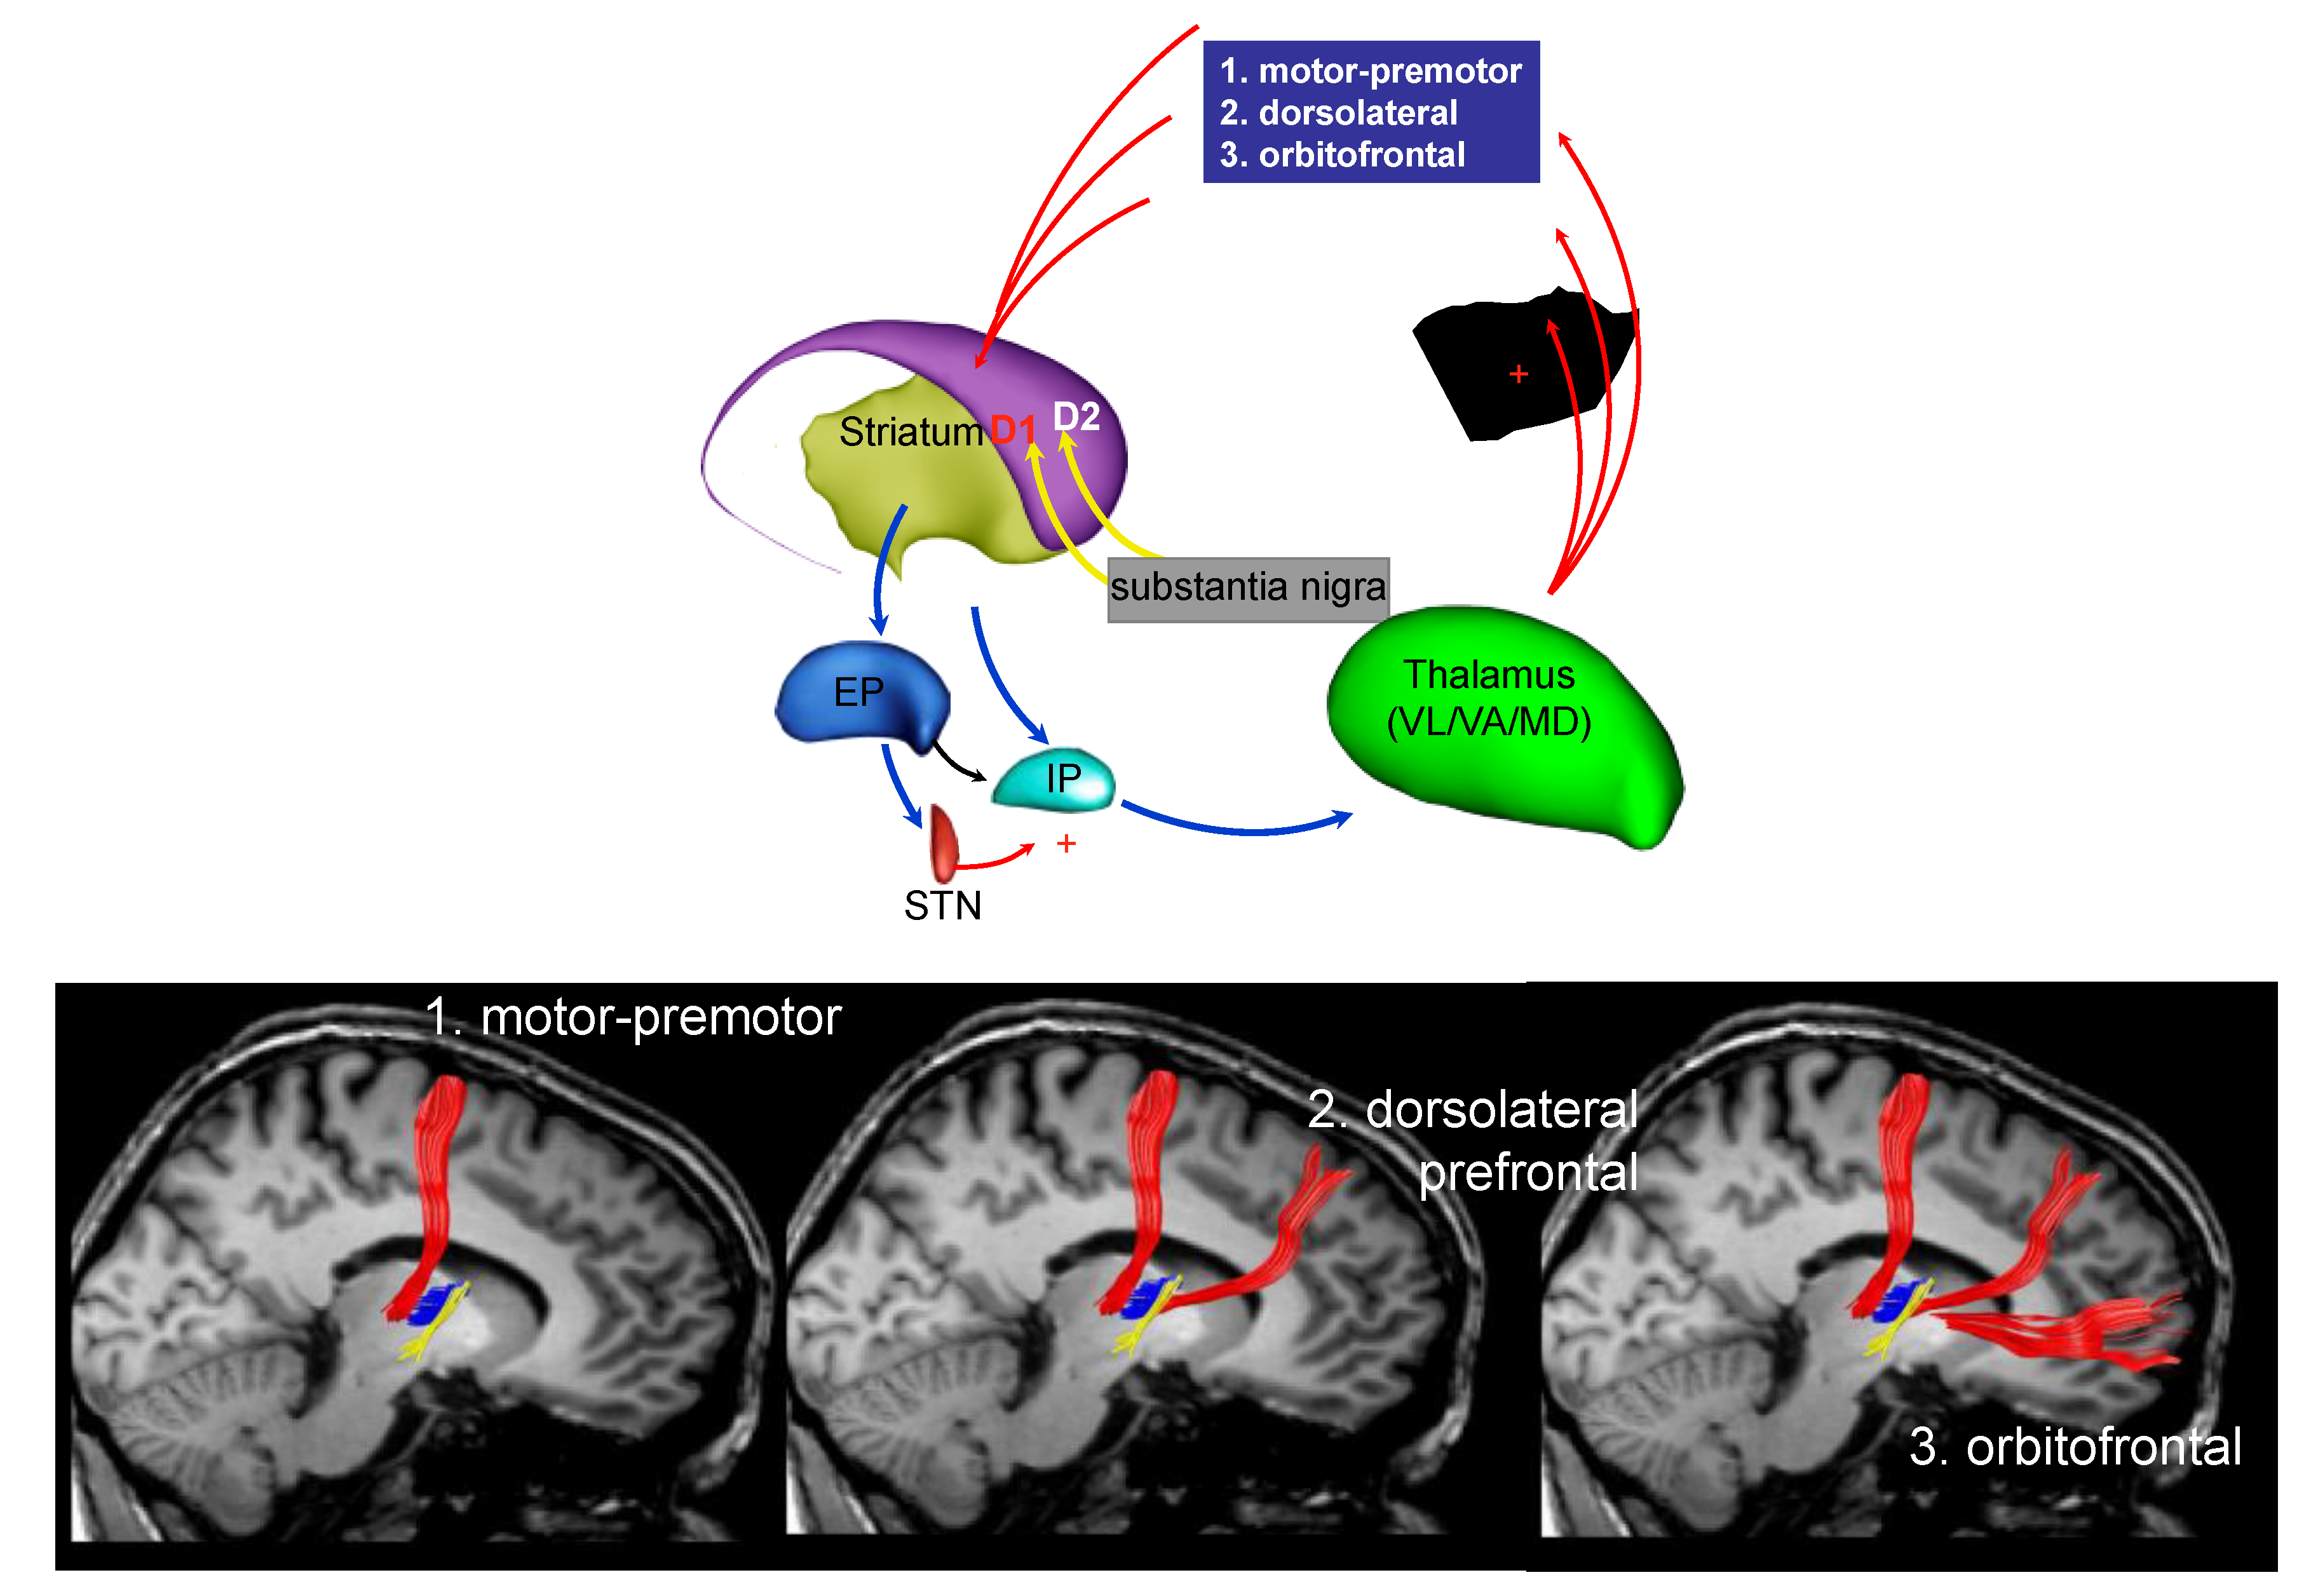

3. Parkinson’s Disease Subtypes Identified by Tractography